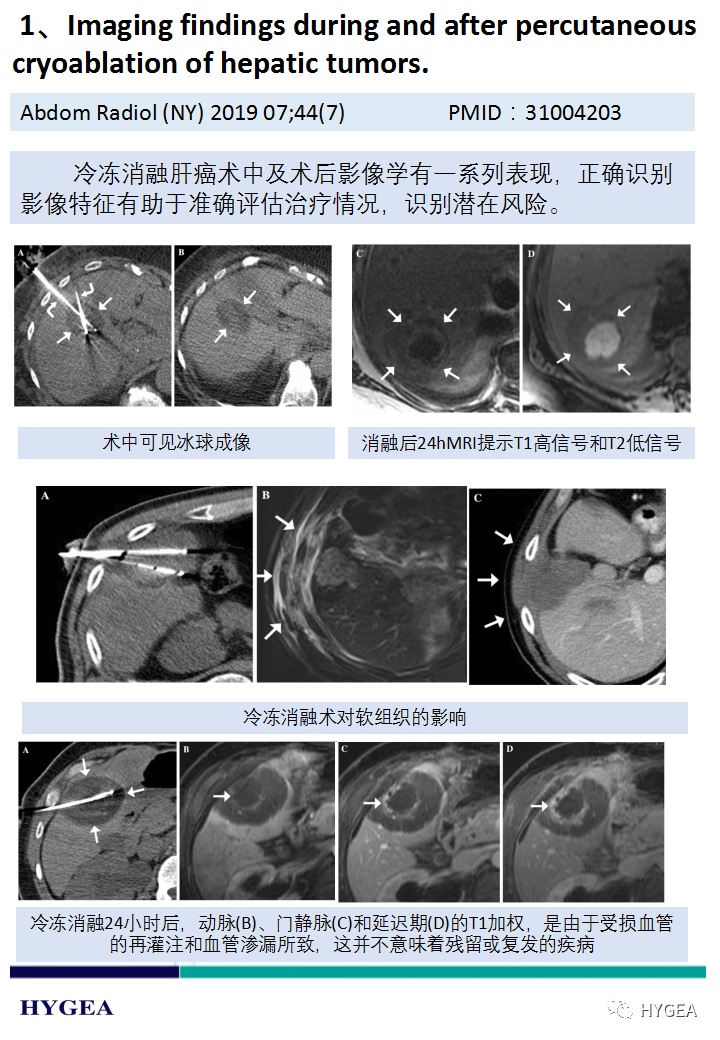

【海杰亞科研資訊】第187期——冷凍消融肝癌專題